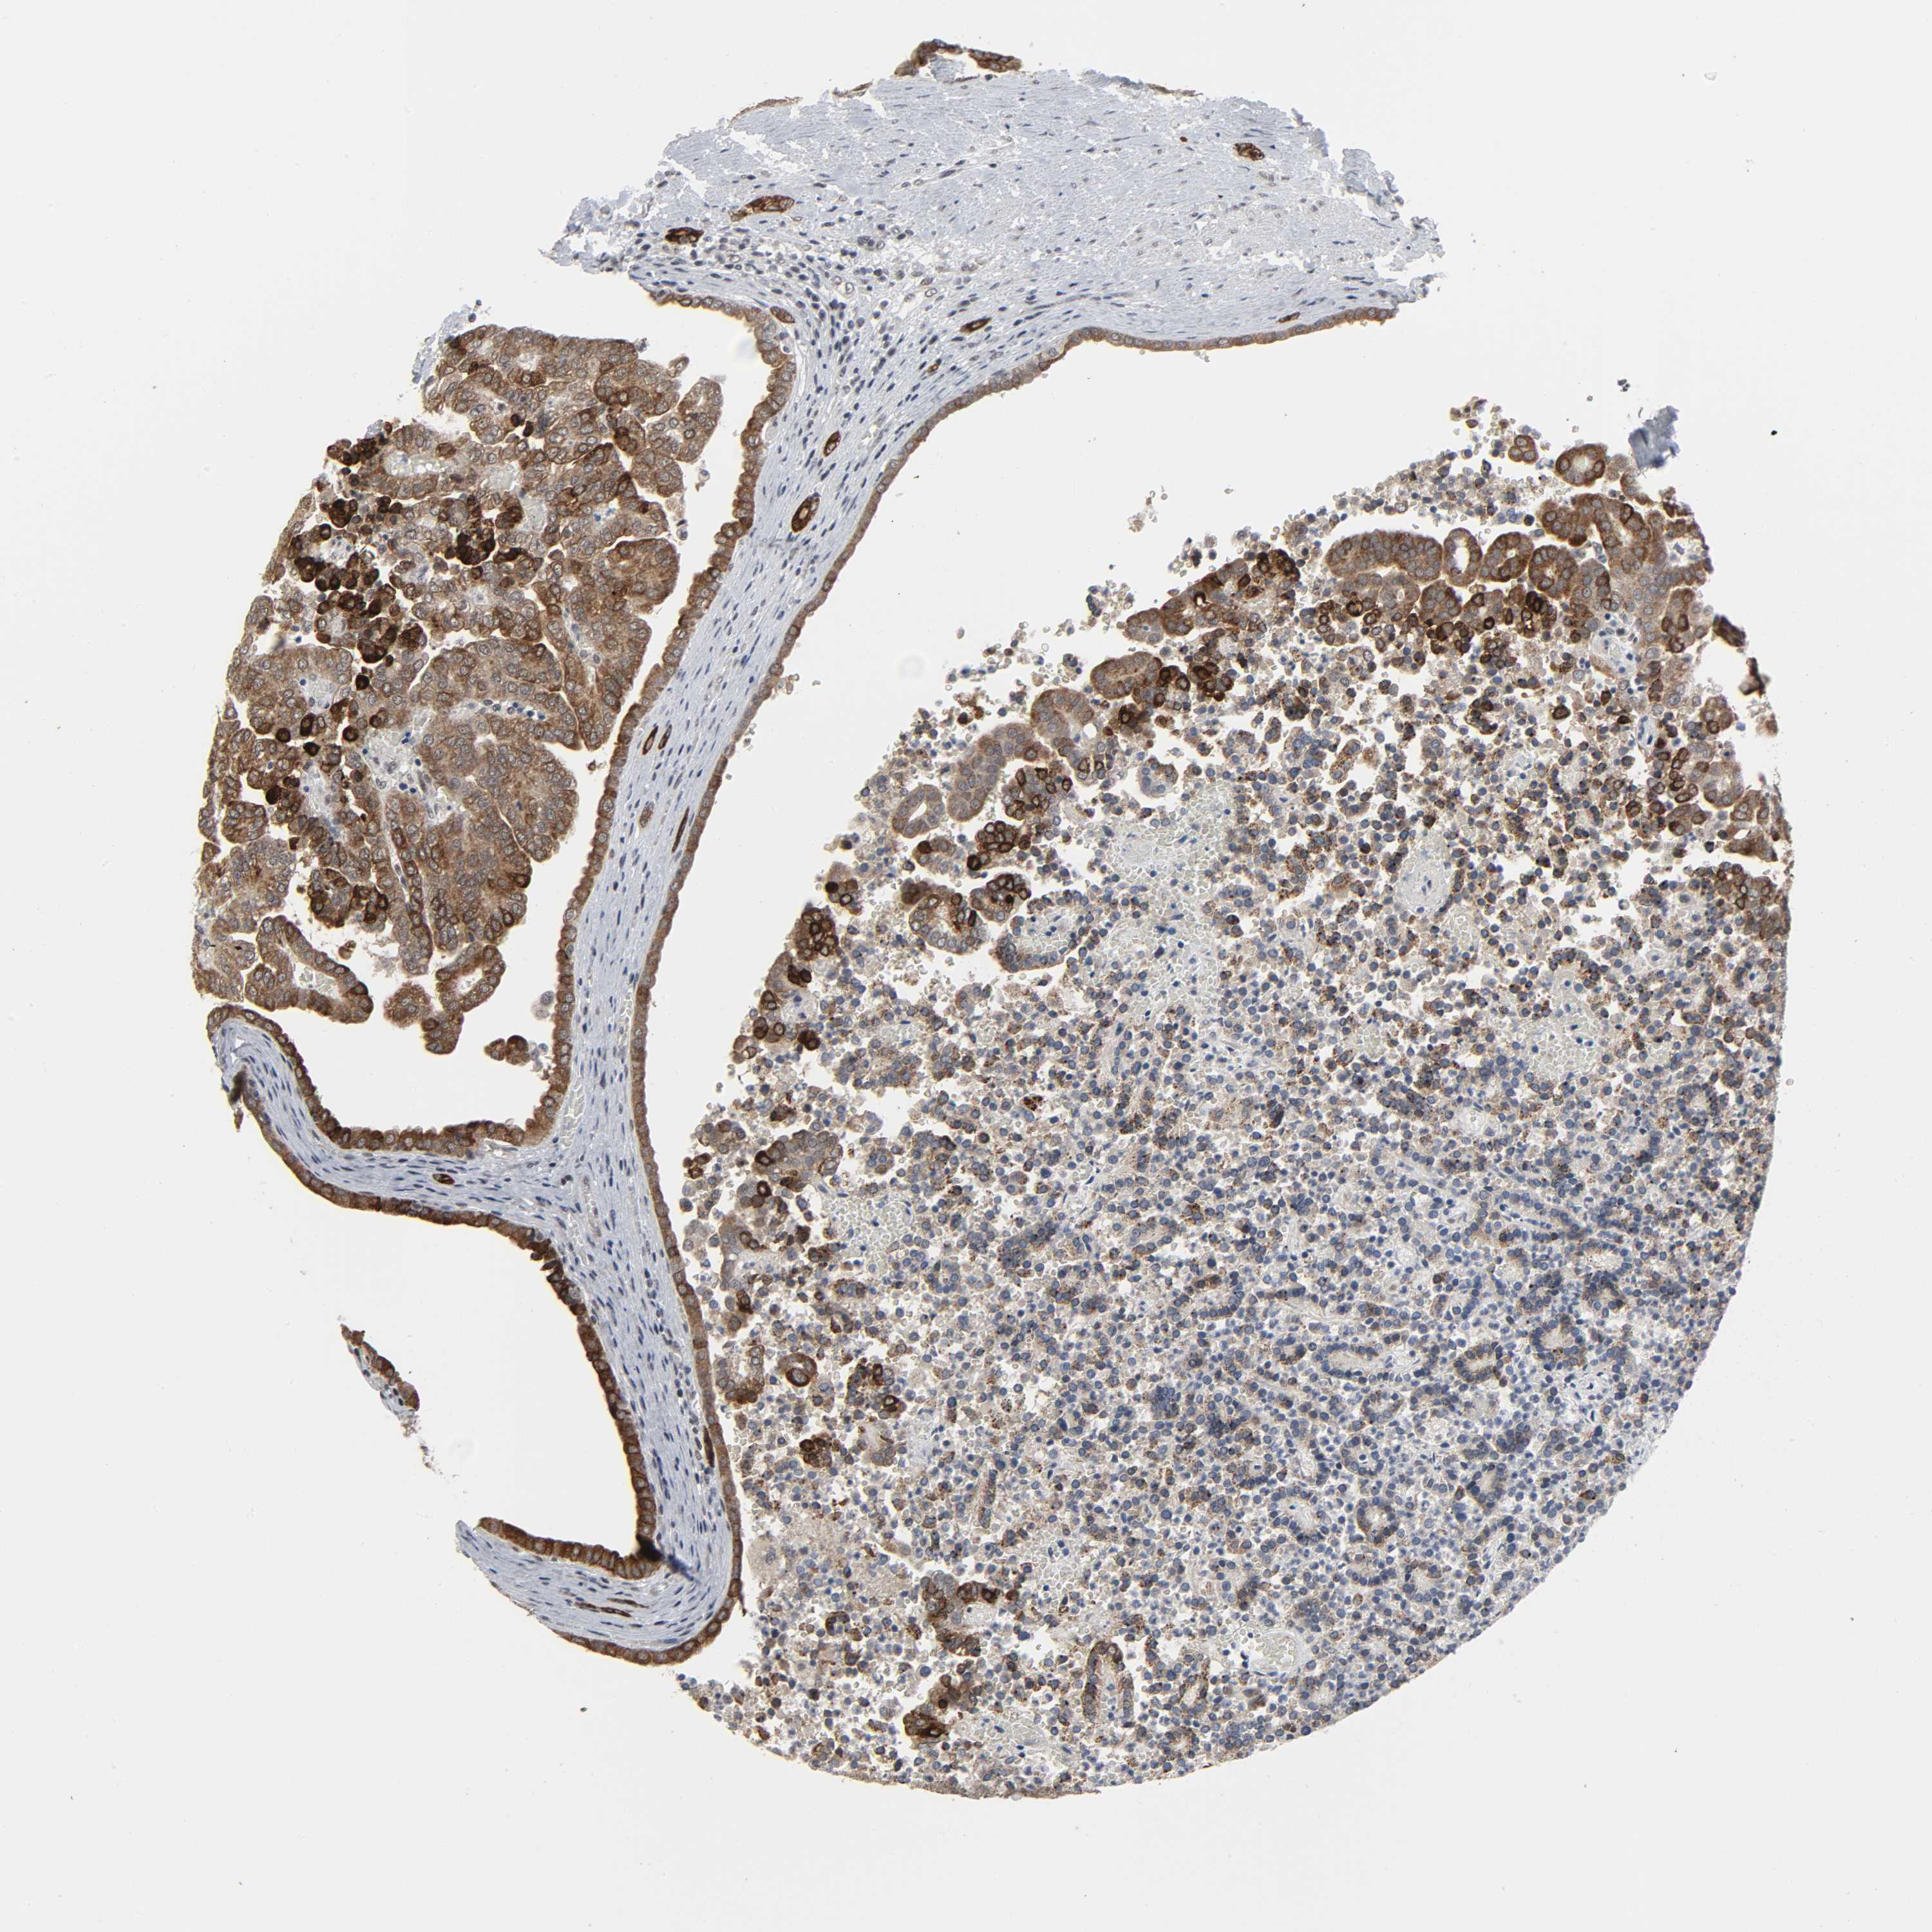

KIDNEY RENAL PAPILLARY CELL CARCINOMA (TCGA) - Interactive survival scatter ploti

MUC1 is not prognostic in Kidney Renal Papillary Cell Carcinoma (TCGA)

& Survival analysisi

Kaplan-Meier plots summarize results from analysis of correlation between mRNA expression level and patient survival. Patients were divided based on level of expression into one of the two groups "low" (under cut off) or "high" (over cut off). X-axis shows time for survival (years) and y-axis shows the probability of survival, where 1.0 corresponds to 100 percent.